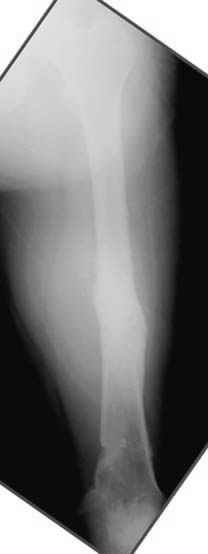

Djoldas Kuldjanov 23 Ноябрь 2004, 18:21

пластическая модель; и коррекция бедра аппаратом Илизарова.

хотя даже если бы и инфекция , то nail exchange с рассверливанием канала - вариант дебрайдмента) Я думаю, что последовательность развития событий:

Узкий к-м канал - тонкий гвоздь- усталостный перелом дистальных винтов - развитие нестабильности и как ее результат остеолиз вокруг гвоздя - деформация анатомической оси бедра. Похоже, что я понял почему аппарат, а не новый гвоздь:-)

ЕТ - Изначально костно-мозговой канал бедра был узкий, дальнейшее его рассверливание ещё больше скомпрометирует прочность бедра( латеральный кортекс дистального отломка уже истончен), приведет к дефекту наружной стенки - хотя это только мои догадки - хотелось бы знать мнение Джолдаса о выбранной тактике.